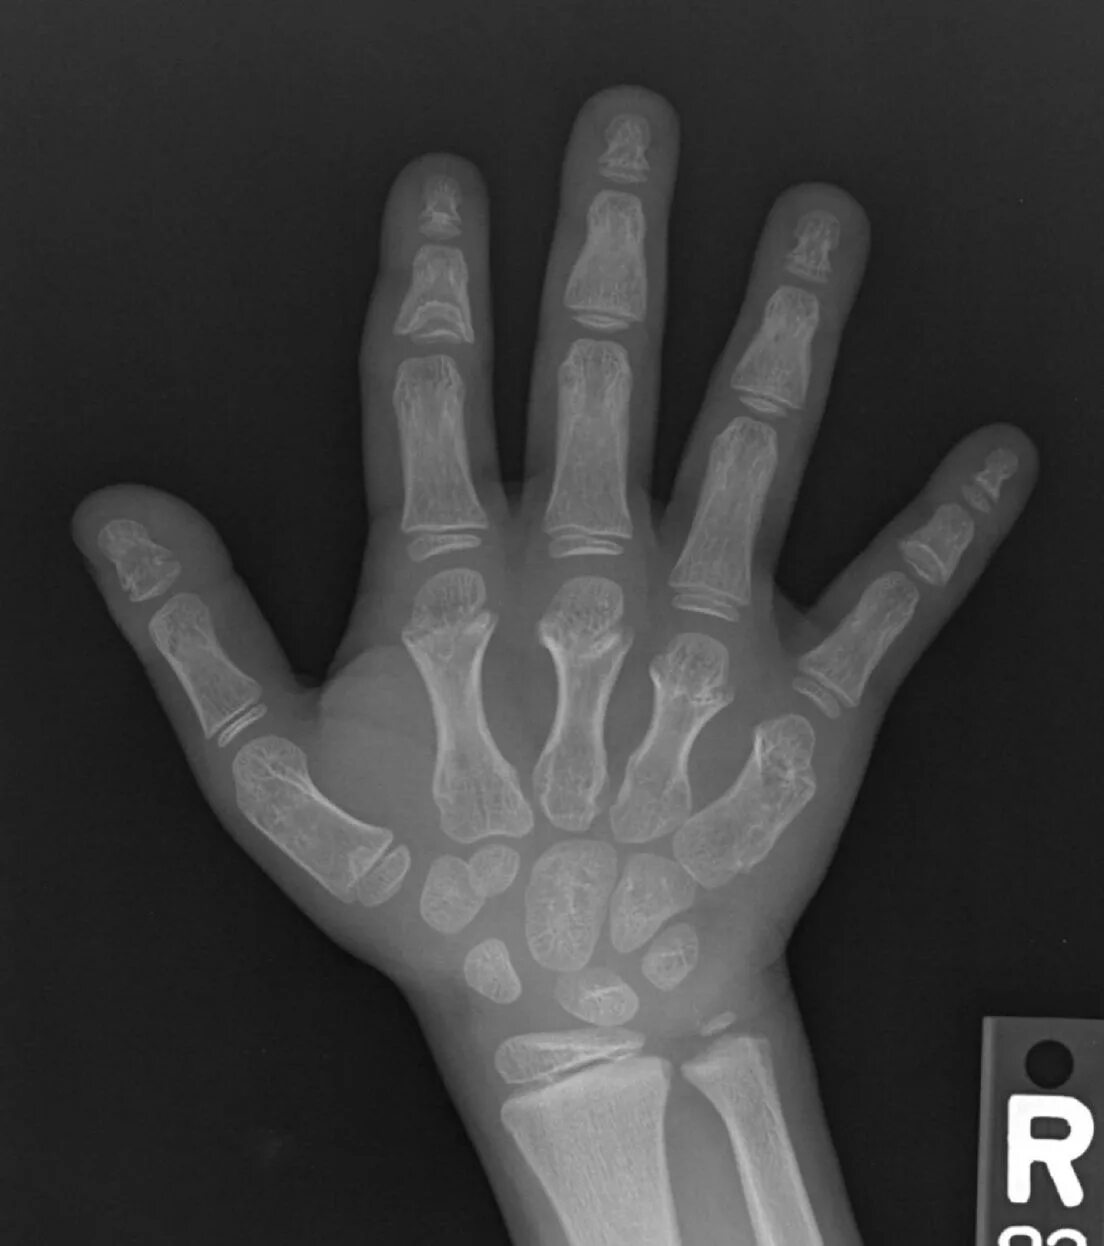

Трубчатые пальцы